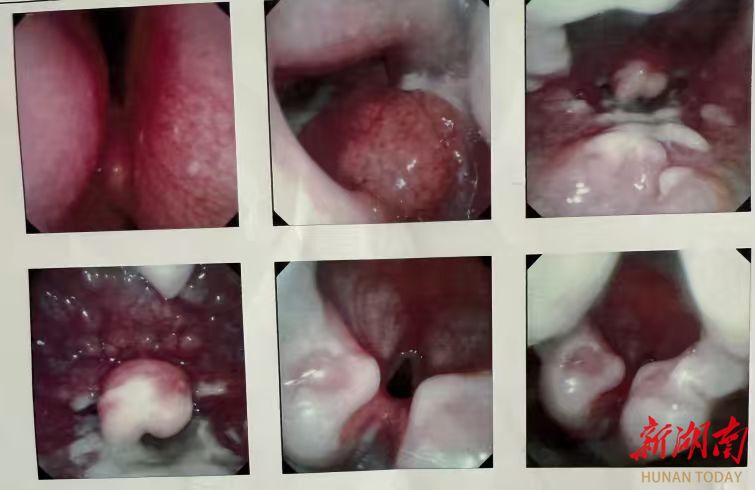

喉镜检查显示咽喉溃疡

接诊的医生检查发现,宁宁咽喉部黏膜大面积充血水肿,部分区域已经出现水疱和糜烂,确诊为咽喉溃疡(烫伤)。细问之下,背后的原因让医护人员既心疼又无奈。